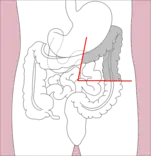

Right hemicolectomy and left hemicolectomy refer to the resection of the ascending colon (right) and the descending colon (left), respectively. When part of the transverse colon is also resected, it may be referred to as an extended hemicolectomy.[5]

Left hemicolectomy

• Transverse colectomy is also possible, though uncommon.

Transverse colectomy

Sigmoidectomy

Total colectomy

Total proctocolectomy